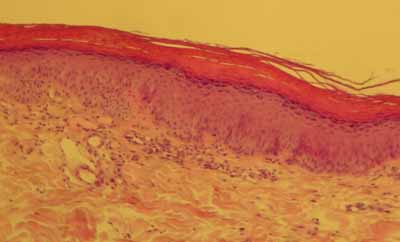

cas-de-parakeratose-granulaire11Photo 11 : Épiderme devenant pustuleux

Le derme en regard, paradoxalement, est peu inflammatoire…… sur une biopsie, on retrouve une lésion de folliculite. Pas de mise en évidence d ‘élément figuré ni parasitaire, ni fongique. On n’observe pas de lésion de vacuolisation hydropique des acanthocytes sous-cornés.